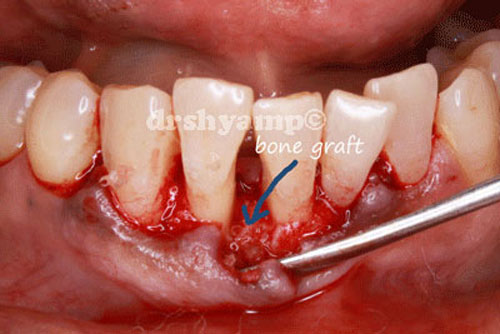

Bone grafting